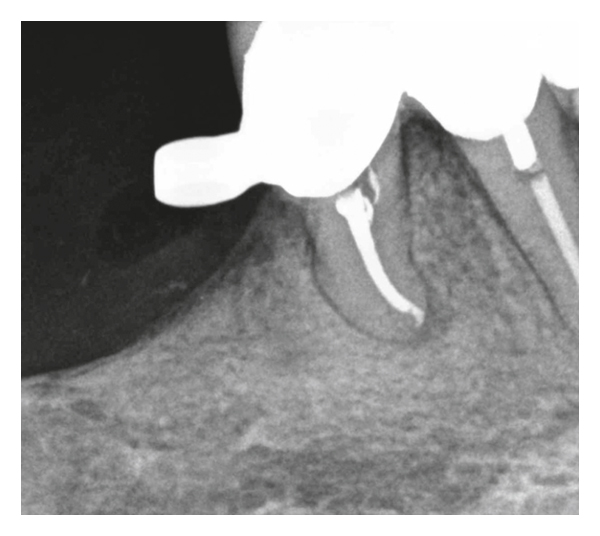

(f)

(g)

After anesthesia with 4% septocaine with 1 : 100,000 adrenaline (Ubistesin Forte, 3M ESPE, Seefeld, Germany) and rubber dam isolation (Hygenic Dental Dam, Coltene Whaledent, Langenau, Germany), the coronal restoration and all root canal filling materials were removed from the mesiolingual and distal canals, but the orifice of the mesiobuccal canal could not be located clinically under the dental operating microscope. Ultrasonics were used to treph along the isthmus area at a position where the orifice of the mesiobuccal canal was estimated to be. After trephing a 1 mm deep groove at the mesiobuccal canal position, the orifice could not be located. A GP point was placed and compacted at the depth of the groove (Figure 2(b)). Following that, a cotton pellet moistened with sodium hypochlorite was placed, and the access cavity was temporarily sealed with 4 mm of Cavit G (3M ESPE, Seefeld, Germany). The patient was referred for limited FOV CBCT (Morita 3D Accuitomo 170, J. Morita MFG Corp., Irvine, CA, USA). The axial view of the CBCT revealed that the canal was located 0.5 mm buccally to the GP point, and calcification was evident (Figure 2(c)). Furthermore, the canal seemed to be patent 2 mm apically to the GP point (Figure 2(d)). The sagittal view of the CBCT revealed that the orifice of the mesiobuccal canal was located 0.5 mm mesially to the GP point (Figure 2(e)). At the second visit, temporary filling materials were removed, and ultrasonic preparing was performed buccally and mesially to the GP point. A microopener No. 10/.04 (Dentsply Maillefer, Tulsa, OK, USA) was introduced into an opening located at the estimated distance according to the CBCT, and the presence of the canal was confirmed using an apex locator (Root ZX II, J. Morita MFG Corp., Irvine, CA, USA). Root canal preparation was carried out using an endodontic rotary instrumentation system (Race, FKG Dentaire SA, La Chaux-de-Fonds, Switzerland) up to a 35/0.4 file. Sodium hypochlorite 2.5% was used for copious irrigation. The canal was filled with GP and epoxy sealer (AH Plus, Dentsply Maillefer, Tulsa, OK, USA) using warm vertical compaction. The access cavity was sealed with composite resin, and a postoperative radiograph was taken (Figure 2(f)). The patient was recalled yearly for clinical and radiographic follow-ups. At two-year follow-up, the tooth was asymptomatic, and periapical healing was observed radiographically (Figure 2(g)).